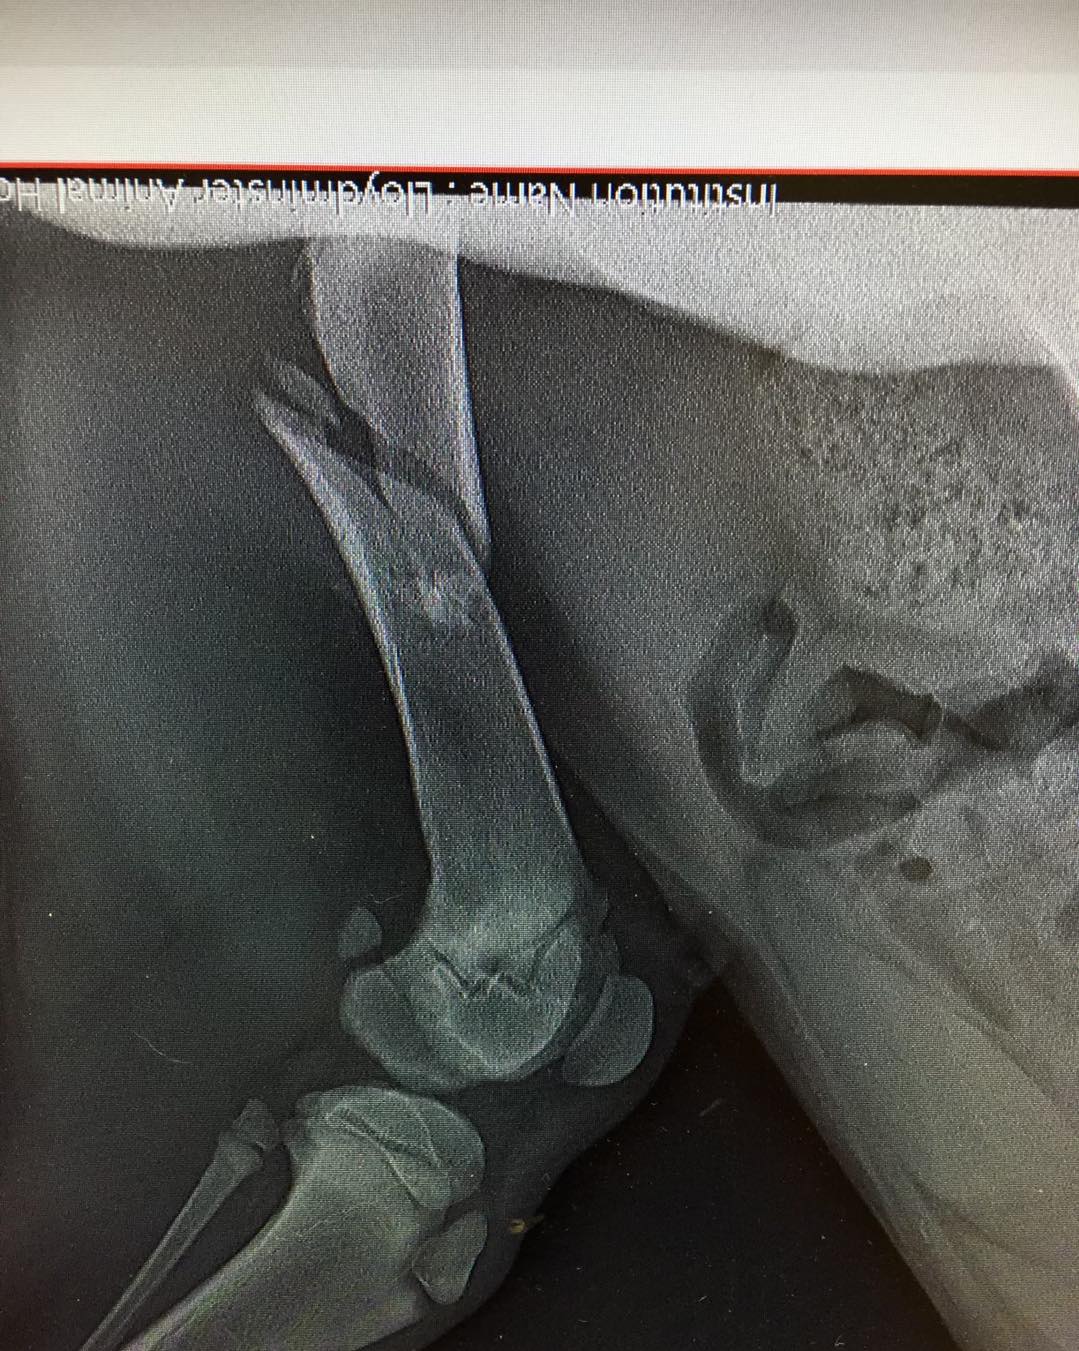

Xena (1)